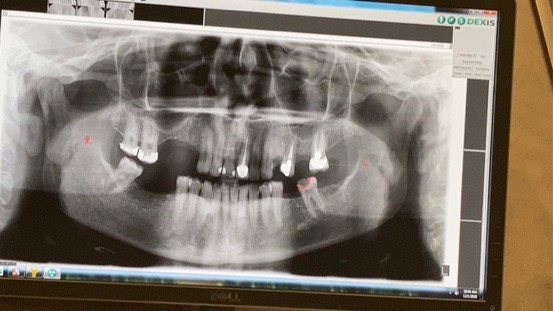

The dental work I need is extensive and medically necessary, estimated to cost between $30,000–$40,000. I’m missing almost all of my back teeth, and all my fronts have cavities. It’s almost impossible for me to eat anything at this point. I will post photos more recent of X-rays soon. The one on here is from a few years ago there’s a few more teeth missing now but you get the picture. On top of that, I will need time off to recover, which adds living expenses I can’t cover while I’m unable to work. That’s why I’m setting my goal at $50,000 to get the treatment I need and make it through the healing period without losing my footing financially.